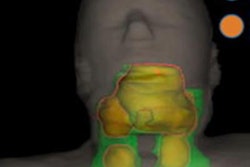

For F-18 fluorocholine PET/CT, the typical appearance is increased tracer uptake relating to a well-circumscribed nodule adjacent to the thyroid, or within the neck or upper mediastinum. Optimizing the PET window settings may help to identify the most accurate focus and thus improve detection of small lesions on the CT component, the Imperial team recommended.

"In [F-18 fluorocholine] PET/CT examinations of the ectopic glands, concordance between second-line imaging is often extremely helpful in cases of unusually located ectopic glands, for preoperative planning, and to minimize risk of morbidity, including scarring and nerve damage," they noted.

Choline uptake can also be seen in inflammation and malignancy, as well as some benign entities such as thymoma and meningioma. Systematic review of the entire study is essential to exclude alternative causes of pathological uptake, they wrote.